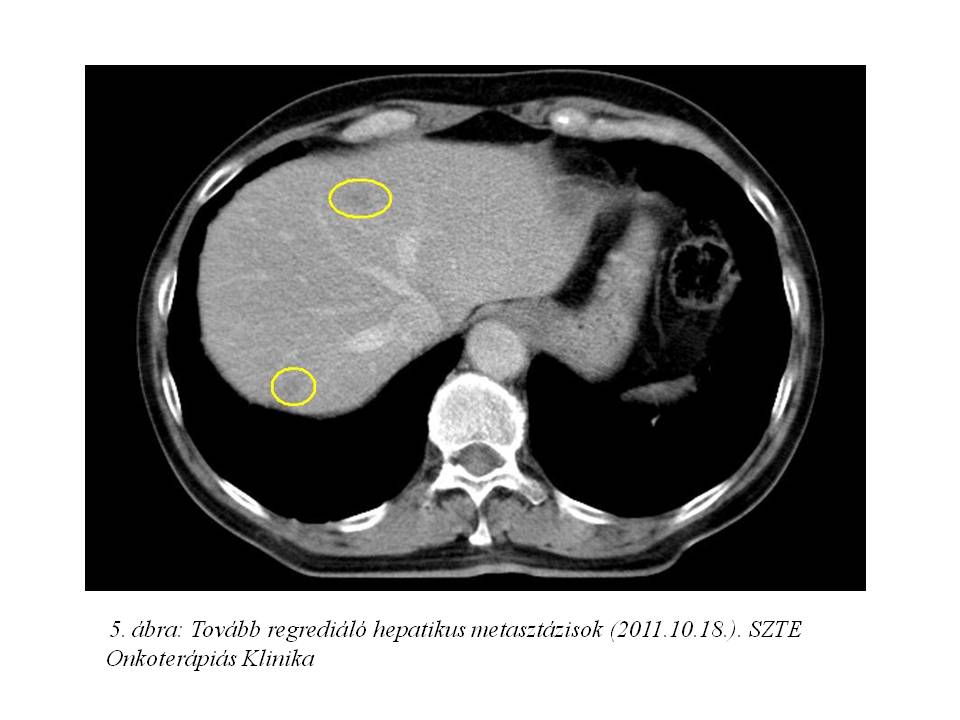

Az akkori staging has-, kismedence CT vizsgálata szerint a primer tumor a bal uretert szűkítette, a májban 4 áttétet írtak le. Mellkas röntgenjén multiplex tüdő áttétek, illetve lymphangitis carcinomatosa lehetősége merült fel. (1. ábra, 2. ábra)

Palliatív onkológiai kezelésként FOLFIRI-bevacizumab immunochemotherápia indult 2011.07.05-től. Az első re-stagingkor (3. ábra, 4. ábra) már parciális remissziót észleltünk (46% csökkenés) mind a primer tumor, mind a tüdő-, mind a máj metasztázisok méretében. 2011.10.18-ára (5. ábra, 6. ábra) a regresszió tovább nőtt (59%). A kezelés mellékhatásaként, az irinotecan infúziót követően jelentkező orrváladékozást (irinotecan okozta specifikus parasympatikus tünet) a további kezelések során sc. atropinnal premedikáltuk, míg Gr.I. postinfúziós vénagyulladását lokálisan kezeltük. A 30. ciklustól a kezeléseket követően émelygés jelentkezett, mely otthon szedett ondansetron hatására megszűnt. Az 53. ciklust követően Gr.III-as hasmenés, exsiccatio és Gr.IV. neutropénia miatt hospitalizálás vált szükségessé. Empirikusan indított intravénás, széles spektrumú, kombinált antibiotikum, sc. filgrastim kezelés, parenterális folyadék-, és elektrolit pótlás hatására állapota rendeződött. Kezelését ezt követően folytattuk, de az észlelt súlyos mellékhatások miatt 25%-os redukciót alkalmaztunk a kemoterápiás szerek dózisában.